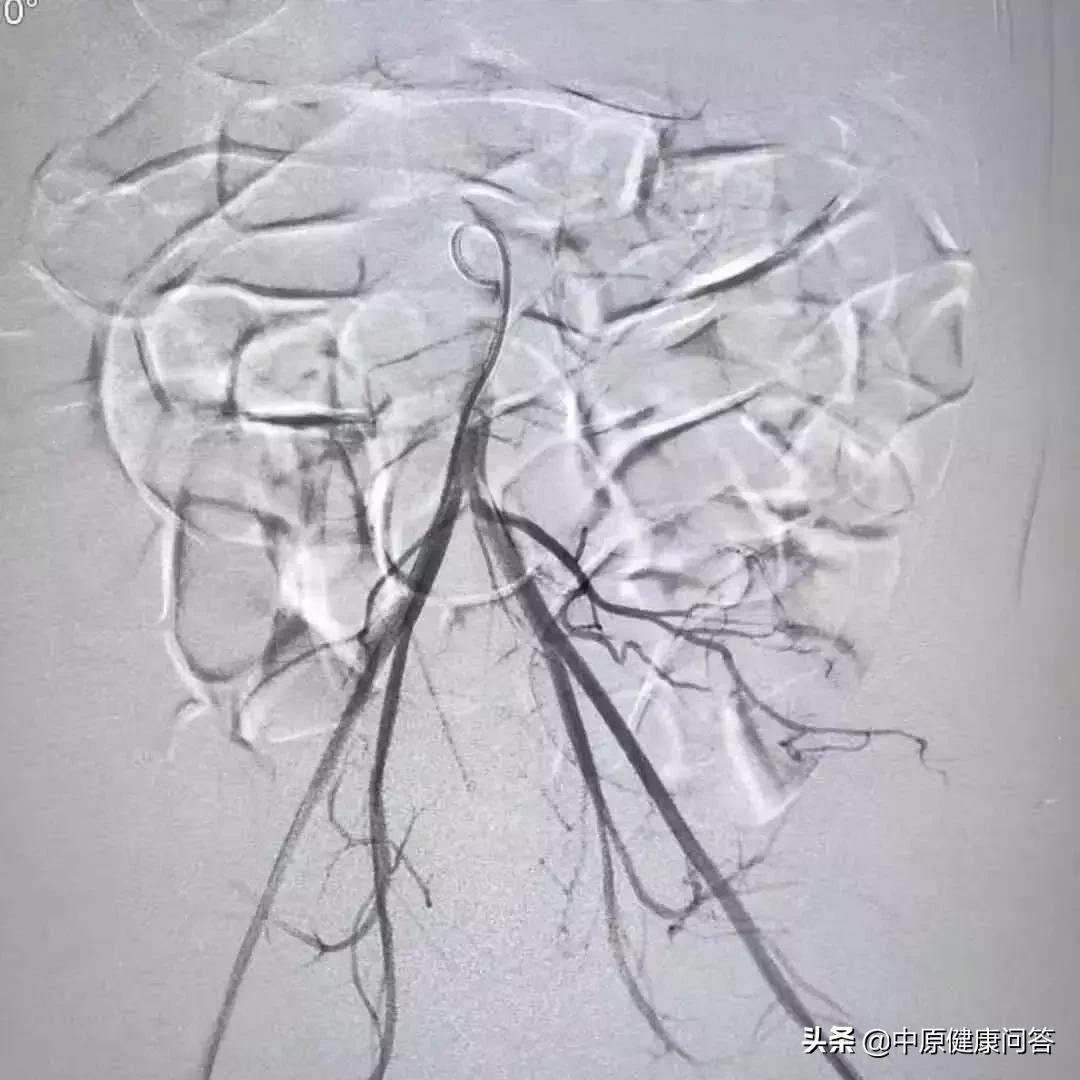

术前造影

手术台上,狄奇操作起DSA数字减影血管造影器,为涵涵的血管瘤部位拍摄清晰的“写真”。在机器的拍摄下,涵涵病变部位复杂、扭曲的血管像树根一样缠成一团、触目惊心。狄奇在涵涵右侧腹股沟开了一个小口,将铅笔芯粗细的导管和导丝沿小口置入血管内。在DSA 的帮助下,导管成功进入到涵涵的腹主动脉。

涵涵只有6个月大,血管纤细无比,狄奇一边借助DSA定位,一边精准操作导管。每找到一根目标血管,他便经导管注入药物进行硬化栓塞。经过一个半小时的努力,手术全部完成,在主动脉造影下,涵涵的病灶完全消失。

术后造影